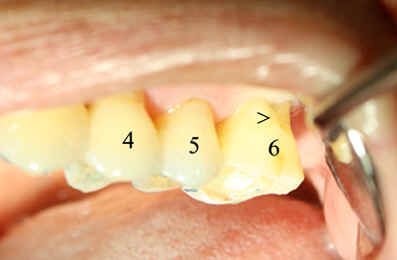

| 图五 牙周手术前左上6号牙颊侧根分叉暴露(箭头) | 图六 牙周手术前左上6号牙舌侧牙龈退缩(箭头) |

检查:6号牙颊舌侧牙龈退缩(图五,图六)